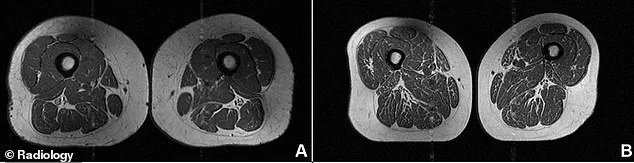

Human thigh muscles can develop white streaks of fat. This process is known as marbling. It looks similar to fat in a steak. A diet high in ultra-processed foods (UPF) can cause this. It directly weakens the muscle tissue.

Through specialized MRI scans, researchers uncovered these hidden changes. They used data from the Osteoarthritis Initiative. The team selected 615 participants from a larger group. None of these individuals had arthritis, joint pain, or chronic diseases.

Each person completed a detailed dietary questionnaire. It covered everything they ate in the past year. Researchers then calculated the percentage of daily UPF intake. They also used MRI scans to grade fat infiltration. This scale ranged from zero to four. A score of four means more than 50 percent fat.

The study appeared in the journal Radiology. It found that higher UPF consumption leads to more intramuscular fat. This effect was visible in the hamstrings, quadriceps, and inner thighs. The link was even stronger when measuring abdominal circumference rather than just BMI.

The inner thighs, or adductors, were most affected. The hamstrings, or flexors, followed next. The quadriceps, or extensors, showed the smallest but still significant effect. These results were consistent for both men and women.